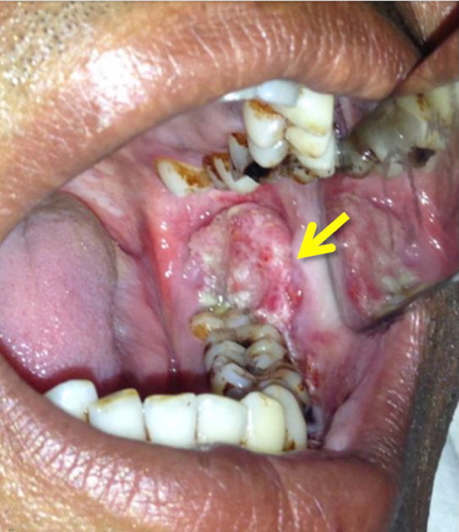

Oral squamous cell carcinoma (SCC) is a malignancy of the oral mucosal epithelium, strongly associated with tobacco, alcohol, and HPV. It frequently arises on the lower lip, floor of mouth, or lateral tongue, and may present as ulcerative or nodular lesions. Precursor lesions such as leukoplakia and erythroplakia are important warning signs. Early recognition and excision are critical, but many cases already show nodal spread at diagnosis.

- Begins as white-gray plaques (leukoplakia)

- Progresses to nodular masses or necrotic ulcers

- Leukoplakia: Well-defined white plaque